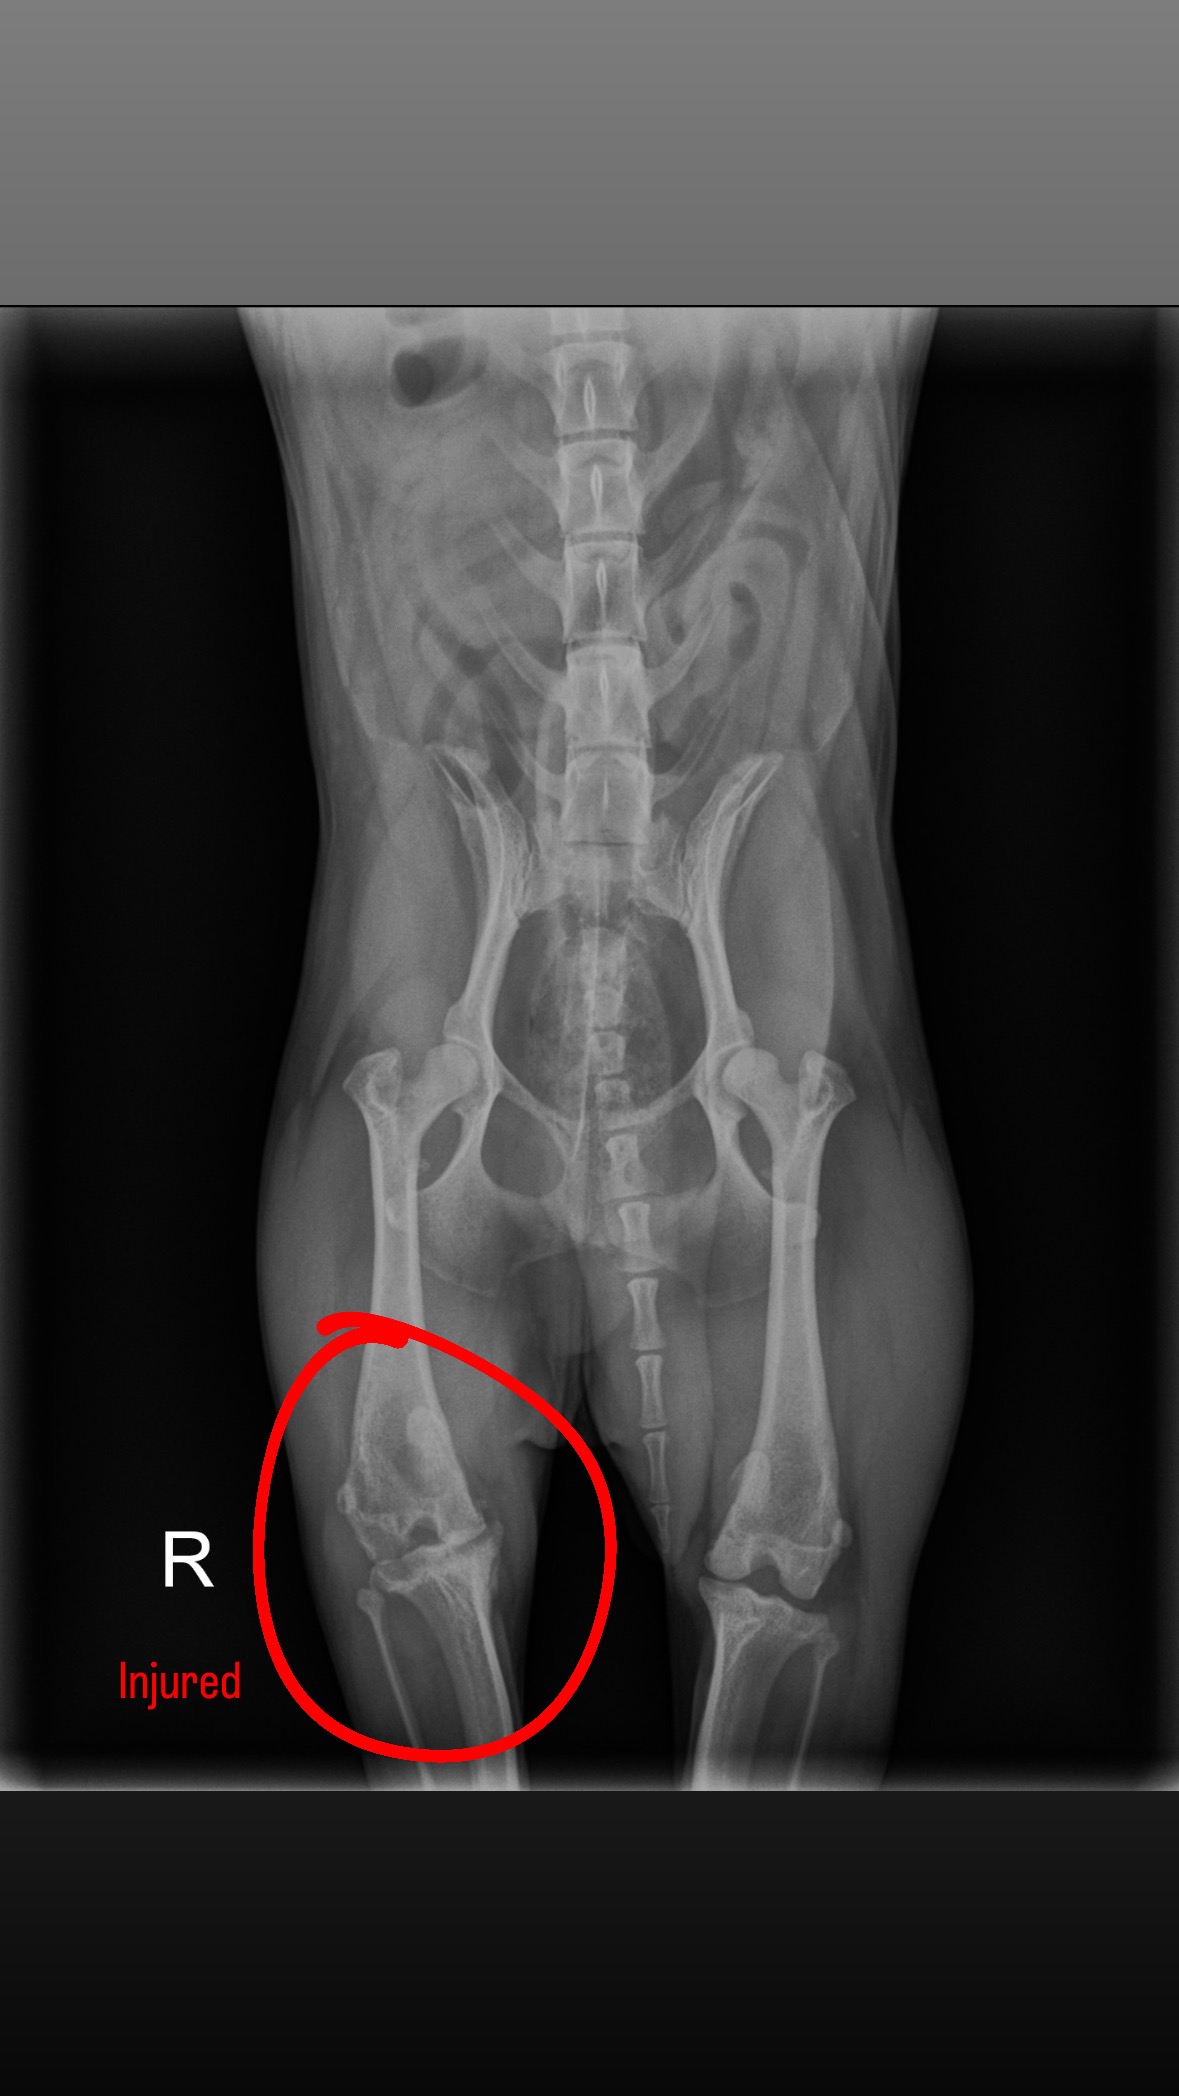

My dog Teddy has a torn cruciate ligament in his right back leg and needs surgery to walk without pain. Right now, he's limping, uncomfortable, and starting to show early signs of arthritis—even though he's only 5 years old. It's hard to watch him struggle with something that can be treated, but the cost of surgery is more than I can afford on my own.